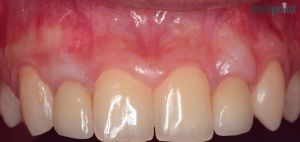

Fémmentes korona és ínyrecesszió fedés

Hölgy páciensünk metszőfogát fémmentes koronával tettük esztétikusabbá illetve visszahúzódott fogínyét ínyrecesszió fedéssel korrigáltuk.

1) Kiindulási helyzet

2) Elszíneződött metszőfog